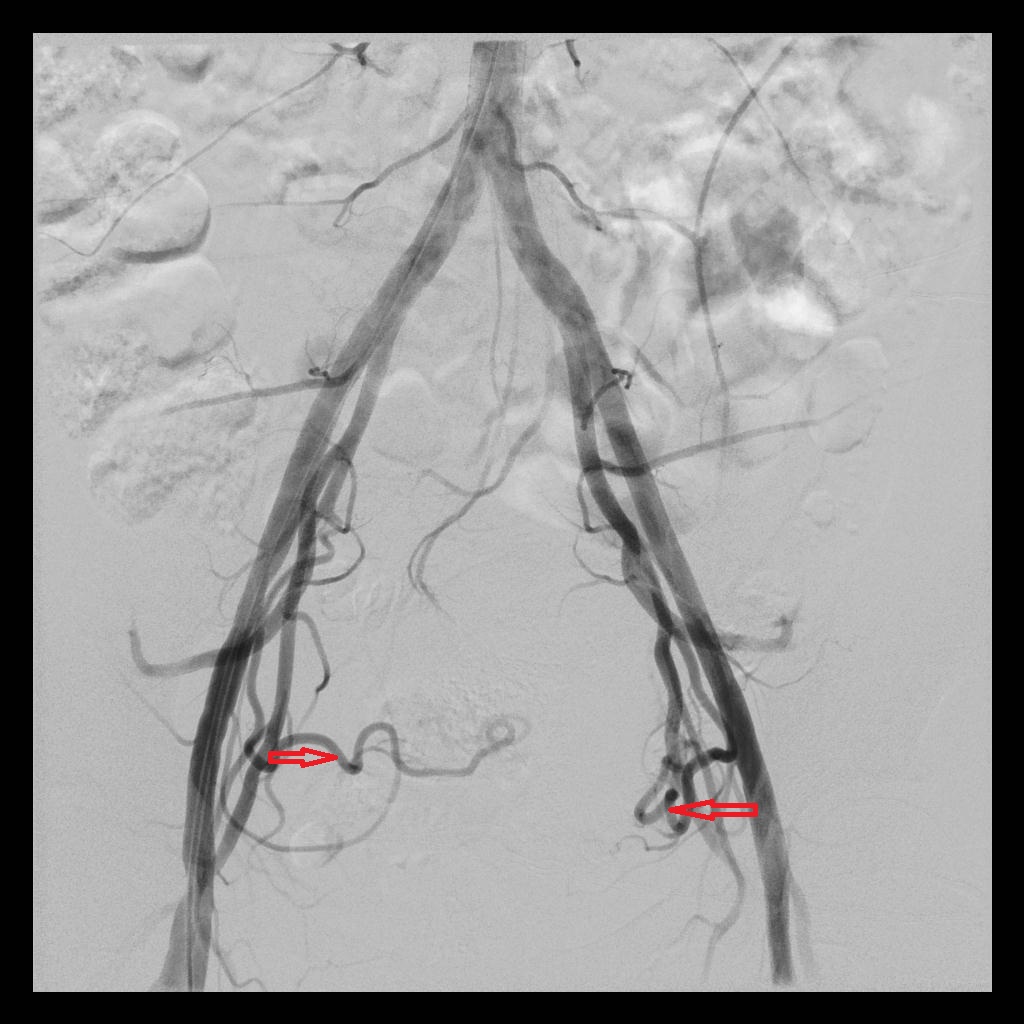

后经腹部主动脉造影显示,子宫双侧的子宫动脉均有增粗、迂曲的情况(下图中红色箭头所示),子宫和子宫肌瘤也均有所增大(下图中绿圈所示)

术后,经子宫动脉造影显示:之前增粗、迂曲、供血丰富的子宫动脉,经栓塞术后,血流基本停滞;之前增大的子宫和子宫肌瘤,经栓塞术后,其造影染色也已消失。

(左侧子宫动脉造影:术前、术后)

(右侧子宫动脉造影:术前、术后)